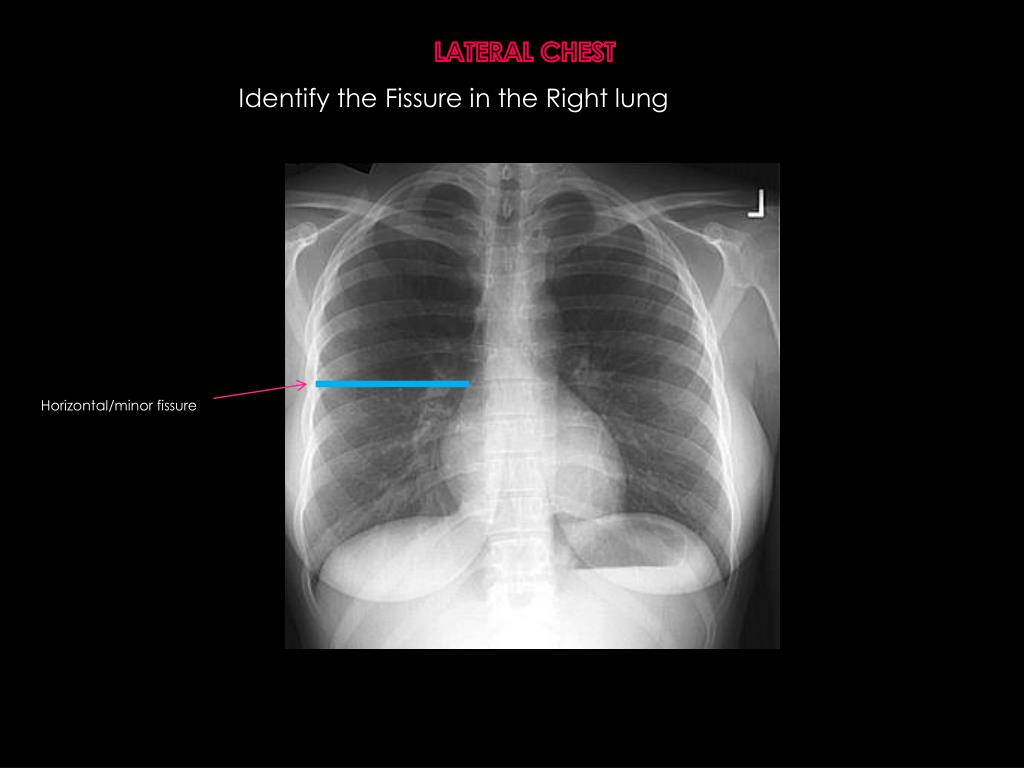

21. LATERAL CHEST Identify the Fissure in the Right lung

22. LATERAL CHEST Identify the Fissure in the Right lung Horizontal/minor fissure